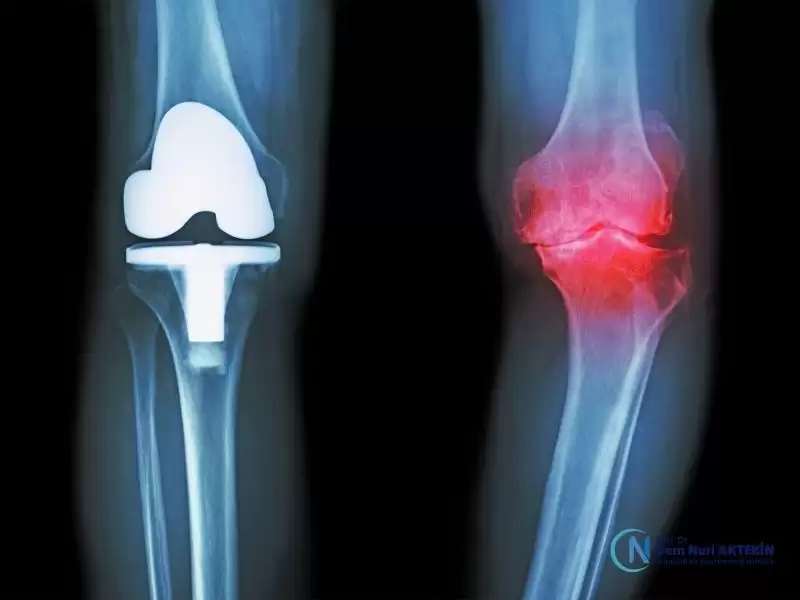

Menisküs Nakli, Total Diz Protezi, Diz Ağrısı, Yarım Diz Protezi, Dizde Kireçlenme, Menisküs tedavileri için cerrahi ve cerrahi olmayan, ihtiyacınıza göre kişiselleştirilmiş tedavi planları ile hareket özgürlüğünüzü yeniden kazanın.

• Protez Cerrahisi